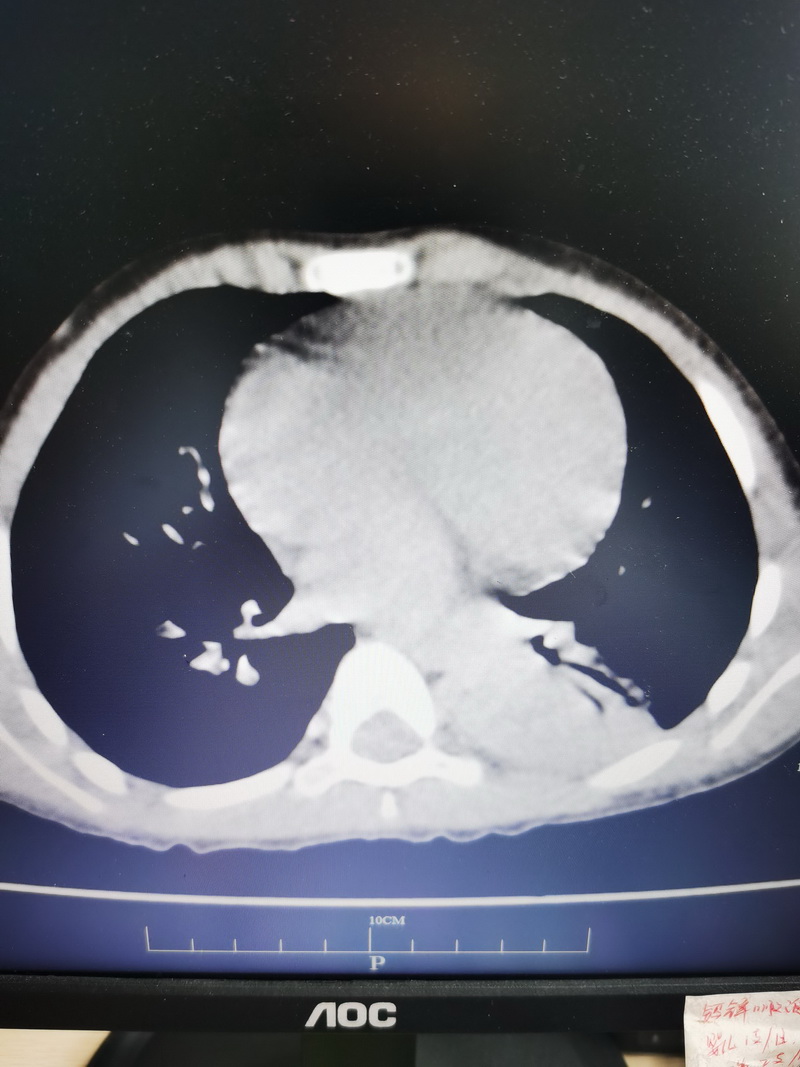

收住入院后,胸部高清CT检查结果显示:左下肺叶实变、左下叶背段气管狭窄。小项的症状一直未得到缓解,与家长沟通并取得同意后,儿科副主任章玲玲决定对小项进行电子支气管镜检查,并行支气管肺泡灌洗术。

▲术前 VS ▲术后